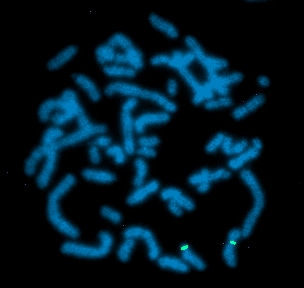

karyotype FITC detects D12S2343, DAPI counterstain |